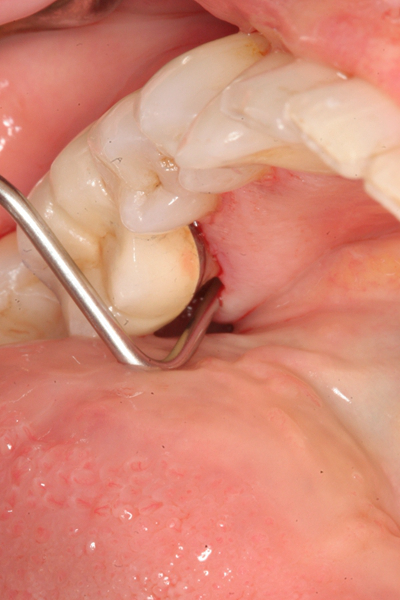

牙齦炎圖片

牙齦炎和牙周炎